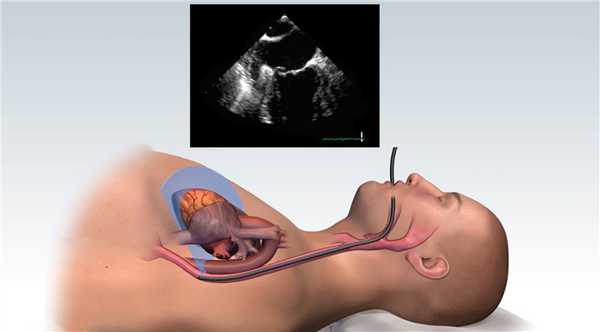

Для уменьшения рвотного рефлекса производят поверхностную анестезию глотки. После в пищевод вводится датчик, расположенный на гибком зонде (методика схожа с гастроскопией). Во время исследования пациент находится в положении на левом боку лицом к врачу, проводящему исследование. Правое колено пациента согнуто и располагается спереди от левой ноги, голова слегка наклонена вперед. Для защиты датчика от перекуса используют загубник. Датчик перед введением обрабатывают ультразвуковым гелем. Введение датчика в пищевод проводится врачом. Датчик располагается в средней части пищевода на уровне сердца. Отсутствие преград для ультразвука и малое расстояние до структур сердца позволяет в разы повысить разрешающую способность исследования и получить информацию, недоступную при трансторакальном исследовании. Исследование длится 5 - 15 минут, что зависит от объема требуемой информации.

Чреспищеводная эхокардиография (ЧПЭхоКГ) - метод ультразвуковой диагностики сердца с использованием специального датчика, вводимого через пищевод.

Позволяет улучшить «ультразвуковое окно» и дает возможность значительно лучшей визуализации мелких структур сердца из чреспищеводного доступа.